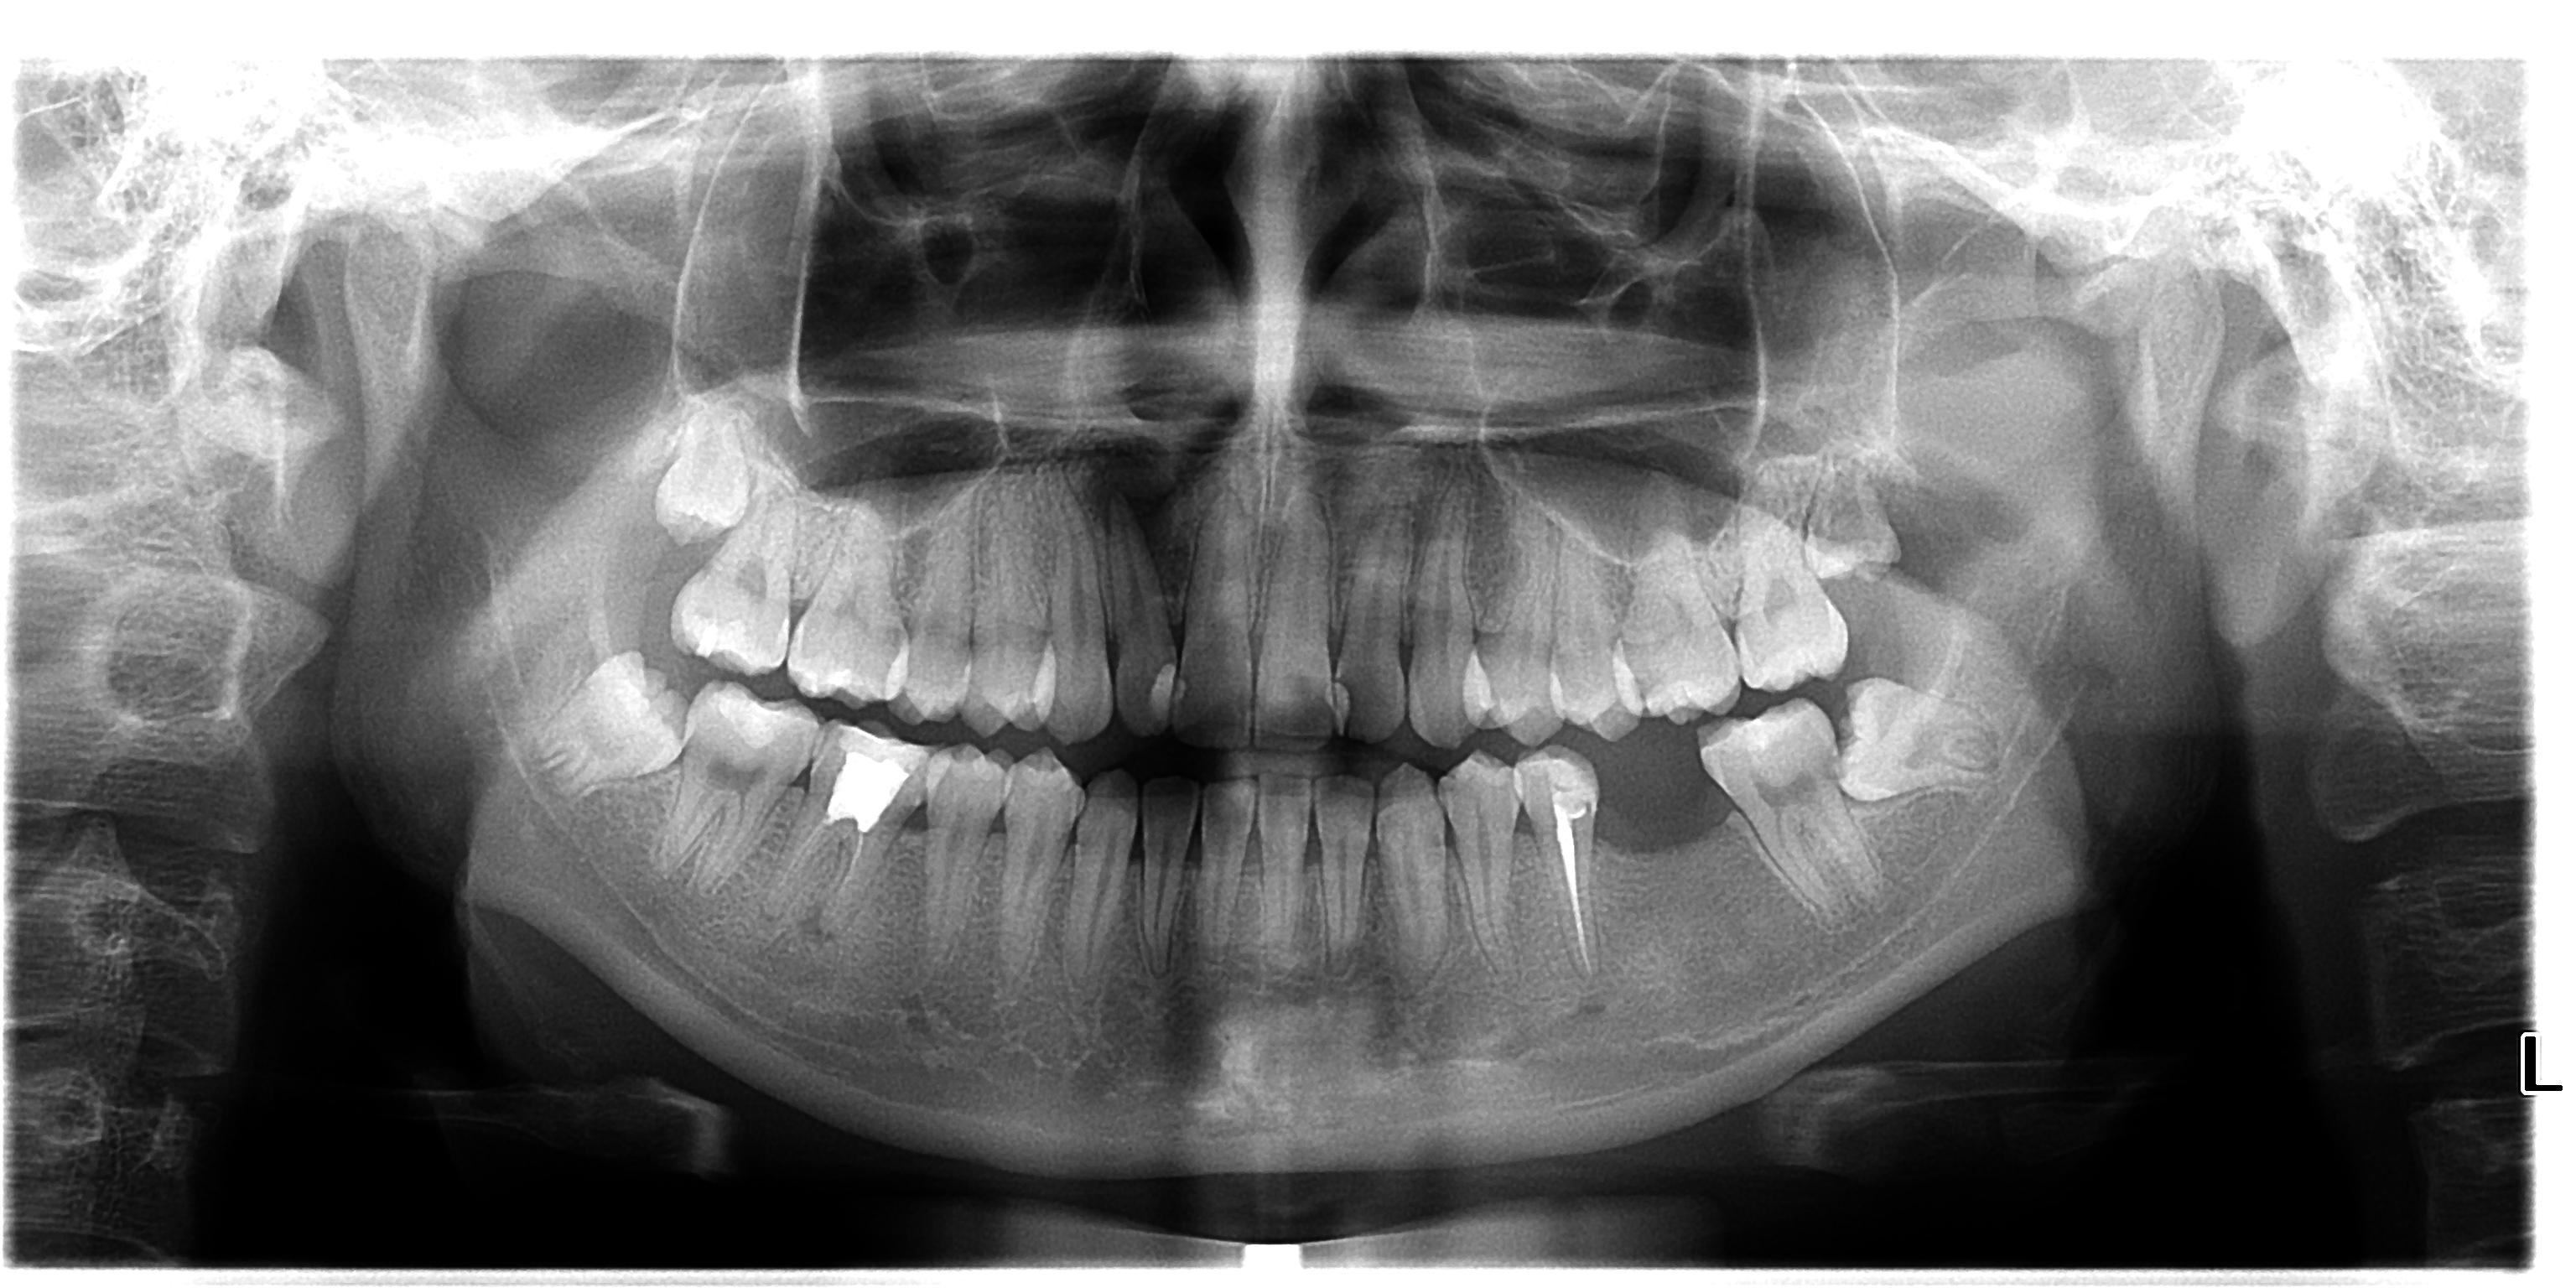

卡瓦口腔全景机价格 (德国卡瓦气动洁牙机)

二手卡瓦单全景机,卡瓦球管、传感器、各个电路板维修更换。